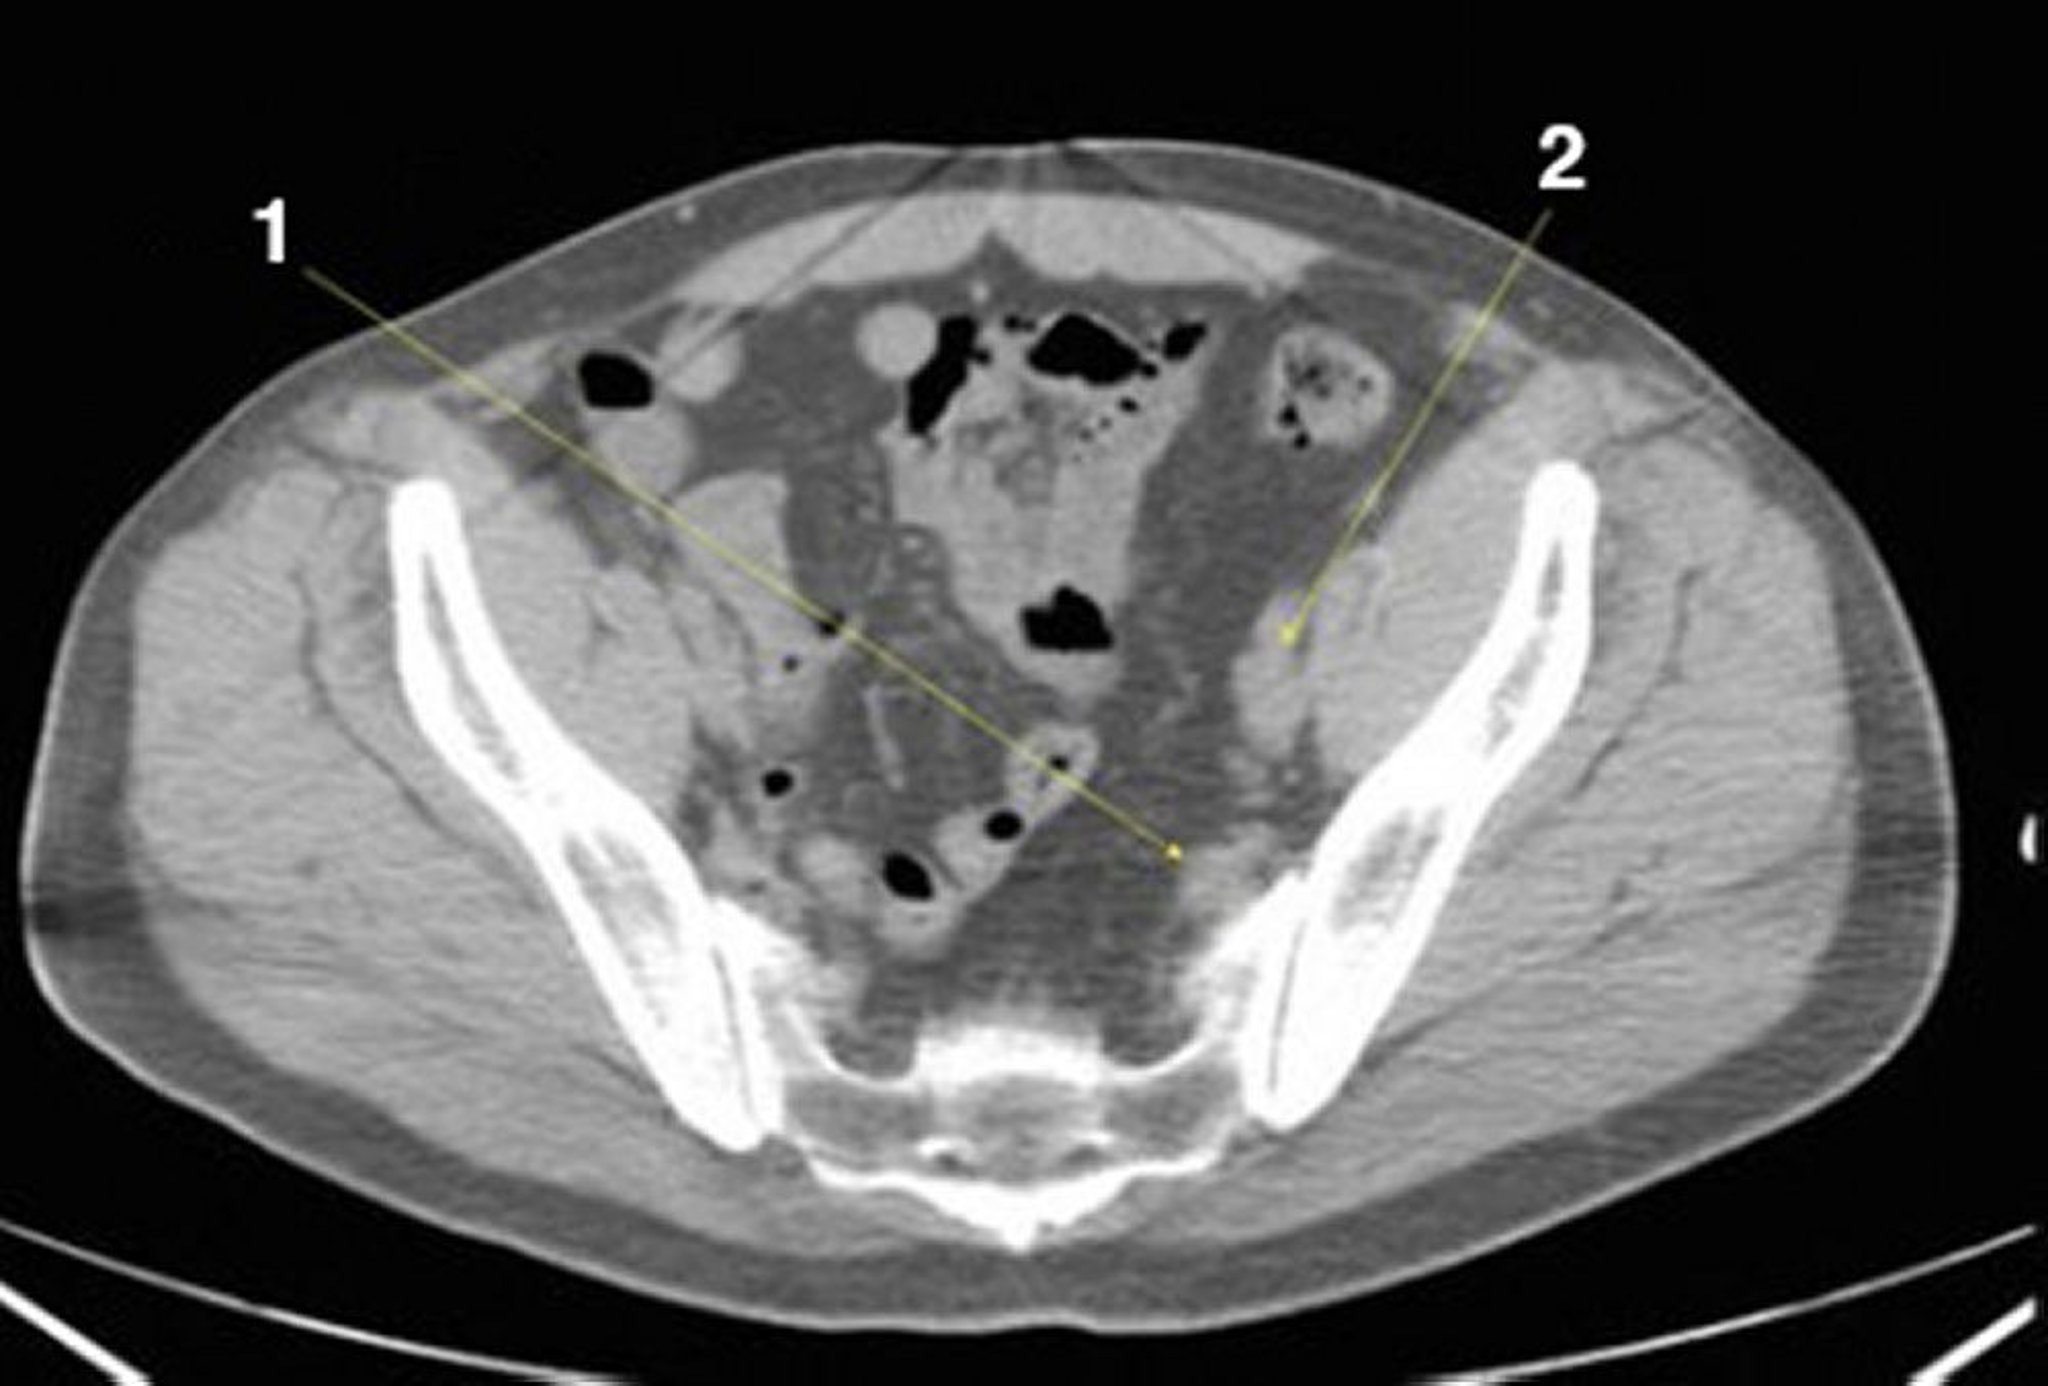

CT-Scan von Abdomen und Becken mit normaler Anatomie ohne Kontrastmittel (Folie 24)

1 = innere iliakale Gefäße; 2 = externe iliakale Gefäße.